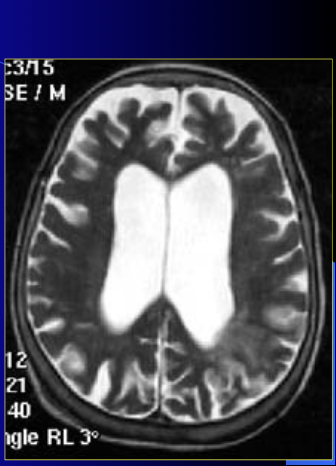

what type of image is this?

how do you know?

what is the enhancement?

T2

CSF is very bright

none